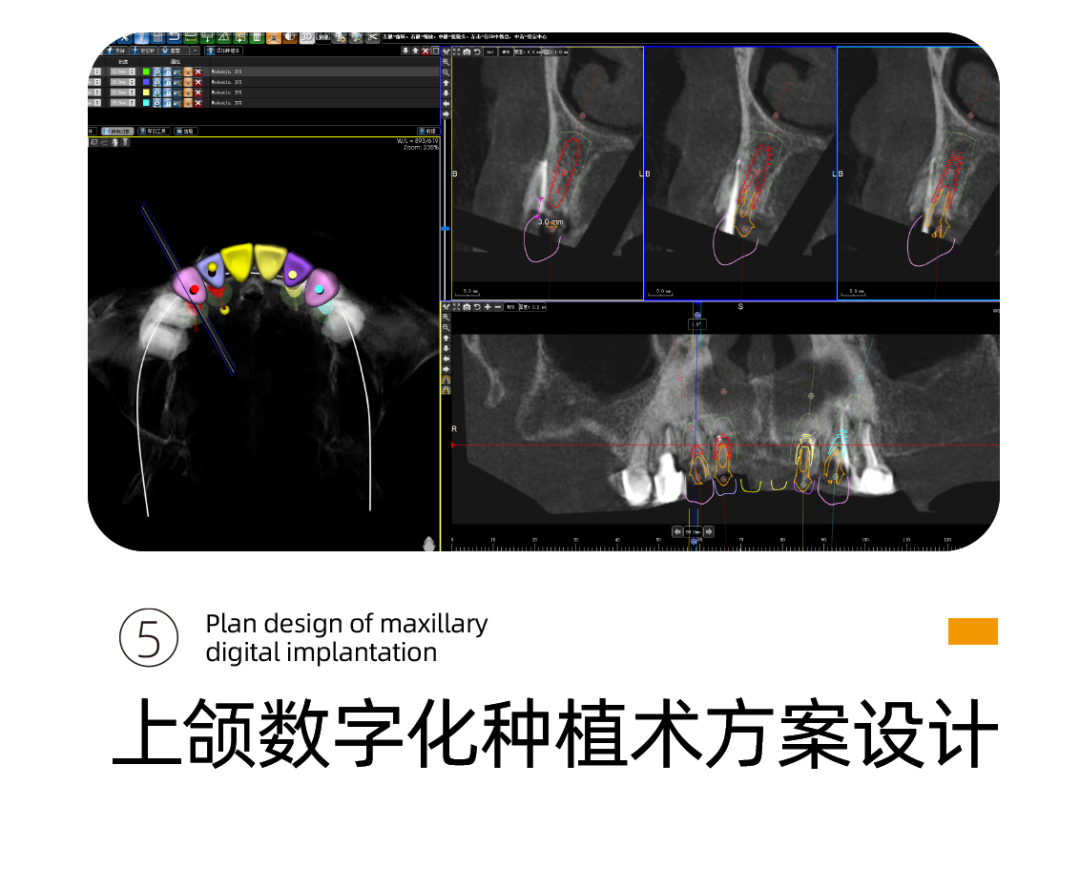

针对阿姨的情况,李雪松院长为阿姨指定全套的数字化种植方案。

什么是UNIC数字化种植方案呢?

其实就是借助Sirona CBCT全景影像信息和相关修复信息为基础,借助数字化专业种植设计软件进行术前诊断和种植方案规划。

UNIC种植体系完美打造专属于患者的“私人订制”完整种植闭环,数字化微创种植结合数字化椅旁修复方式,真正实现当天种植、当天戴牙,其中最大的优点就是可以在术中减少患者的痛苦,提高患者的舒适感。

李雪松院长通过德国数字化口腔扫描设备获取的口内数据完全拟合设计,告别传统种植手术中通过大翻瓣暴露手术区域以及解剖结构的方式,缩短就诊以及手术时间,大幅度降低患者术中的疼痛感。

通过数字化种植手术导向模板,将术前制订的种植方案准确应用于种植手术和即刻修复的全过程,实现以修复为导向的牙种植修复。

换句话说,运用数字化种植技术就是让所有种植操作可以直观得看到,并且能够看得懂。

它的优势在于种植医生借助数字化设备可以真正实现以修复为导向的种植理念,并且实际运用到临床操作中,实现微创种植,不翻瓣,将创口降到最低。

全数字化导板设计会依靠自身数字化的精确定位和微创特点,大大减少失误操作,提高种植手术的精准度。

精准、高效、微创性瞬间提升,伤口更小,出血更少,恢复的更快更好。